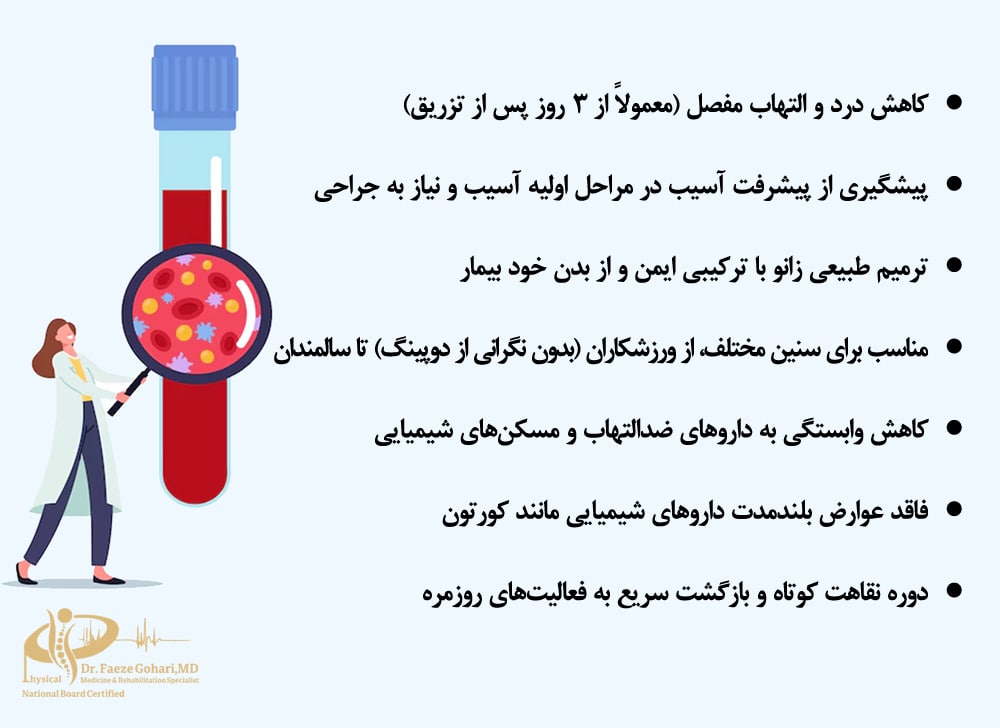

پلاسمای غنی از پلاکت (PRP) یکی از روشهای بازسازیکننده و غیرجراحی است که برای درمان مشکلات زانو بهصورت سرپایی در کلینیک انجام میشود. این روش که برخی بیماران آن را «پلاسما درمانی» یا «تزریق خون به مفصل زانو» مینامند، شامل تزریق پلاسمای غنی از پلاکت خون خود فرد (معمولاً ۳ تا ۶ میلیلیتر) به ناحیه آسیبدیده است.

💉بسته به نوع آسیب، تأثیر PRP میتواند بین ۱۲ تا ۱۸ ماه ماندگار باشد و به همین دلیل در مقایسه با سایر روشهای درمانی، ارزش هزینه به نتیجه بالایی دارد و میتواند از جراحی جلوگیری کند. عوارض این روش نیز به درد و تورم موقت محدود میشود.

🦵این درمان بهویژه در بیماران جوانتر و برای شرایطی مثل آرتروز خفیف تا متوسط، تاندونیت و پارگیهای جزئی رباط صلیبی و مینیسک مؤثرتر است، هرچند محدودیت سنی ندارد و حتی بیماران مسنتر نیز میتوانند از مزایای آن بهرهمند شوند.

فواید تزریق پی ار پی به زانو

مزایای تزریق PRP به زانو قابلتوجه است، بهویژه برای بیمارانی که به دنبال روشی غیرجراحی، کم تهاجم و با عوارض حداقلی جهت کاهش درد و بهبود عملکرد مفصل هستند. همچنین، PRP میتواند بهعنوان گزینهای جایگزین برای تعویض مفصل زانو در موارد آرتروز خفیف تا متوسط یا آسیبهای جزئی به رباطها و مینیسک مورد استفاده قرار گیرد.